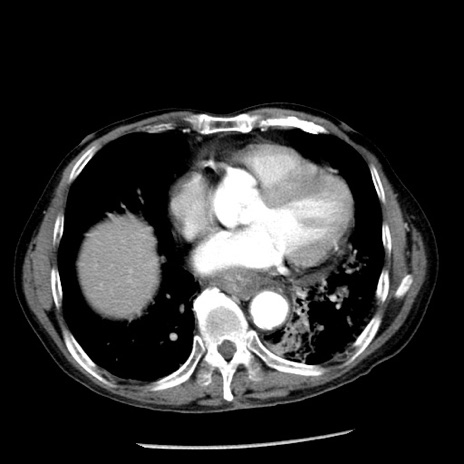

症例26(横断像)

【症例】80歳代男性

【主訴】嘔吐

【現病歴】昨晩2回嘔吐あり、今朝になっても嘔吐あり。来院。

【既往歴】胃潰瘍

【身体所見】意識清明、BT 37.6℃、BP 166/95mmHg、HR 100bpm、SpO2 97%、腹部:平坦・軟、腸蠕動音聴取良好、圧痛なし。

【データ】WBC 21900、CRP 1.46